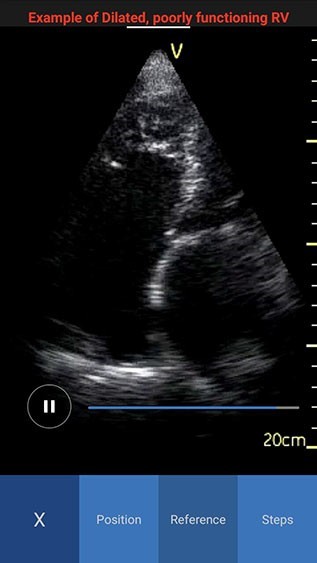

NOTE: By default the reference image tab is activated when you press the info icon for the first time. The white color in the image header represents an example of a normal image, while red color represents an example of a pathology image.

Reference Image Pathology